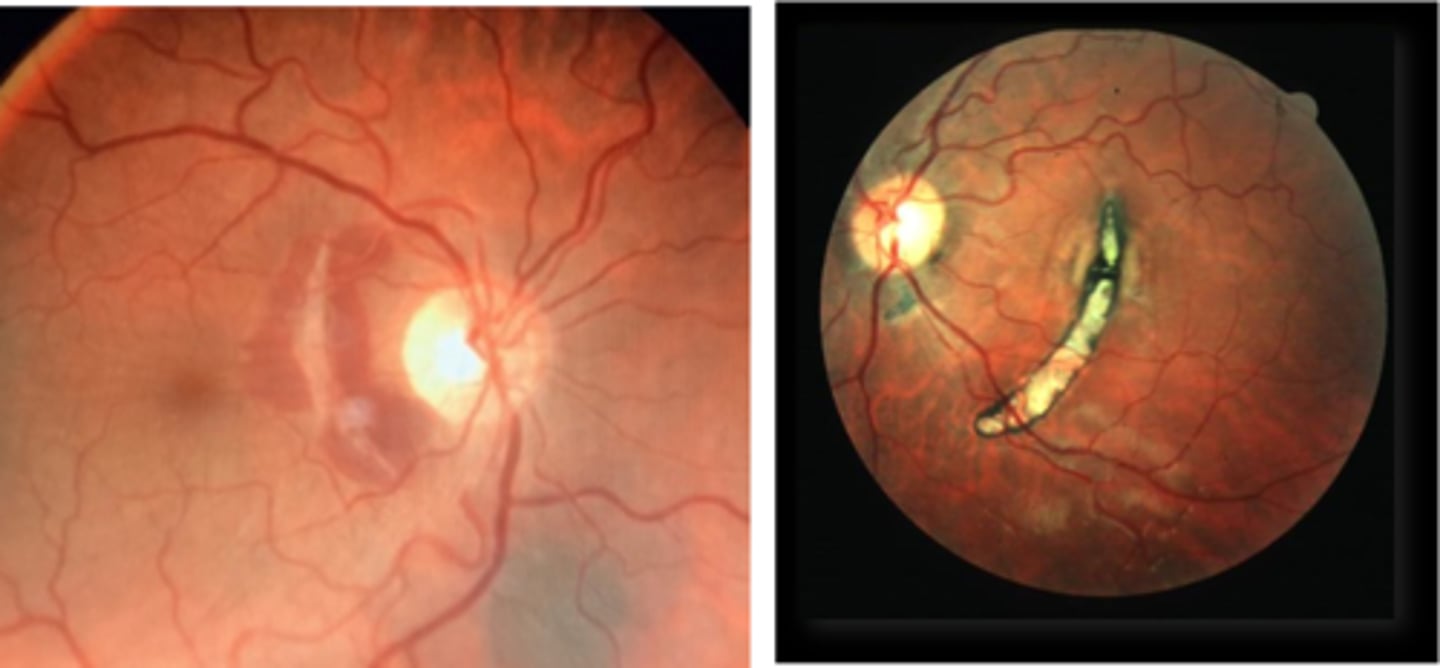

How does choroidal rupture appear on fundoscopy?

curvilinear or crescent-shaped streak, sometimes concentric to ONH

+/- subretinal /subRPE hemorrhage (acute)

Bruch's/Choriocapillaris/RPE damage

overlying neurosensory retina is intact

+/- RPE hyperplasia (chronic)

+/- CNV over time

What findings of degenerative myopia are seen here?

PPA

crescent

lacquer cracks

How do lacquer cracks appear on fundoscopy?

jagged, irregular yellow lines showing sclera in the posterior pole